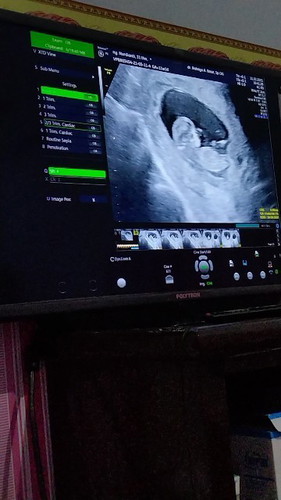

Assalamualaikum Bun saya mau tanya ke Marin zy habis USG dan usia ke hamilan zy bunda sudah memasuki

11W6 hari Alhamdulillah janin sudah terbentuk tapi kata dokter plasentax belum ada apa itu wajar ada kah bunda yg pernah alami hal seperti zya#seriusnanya #ingintahu